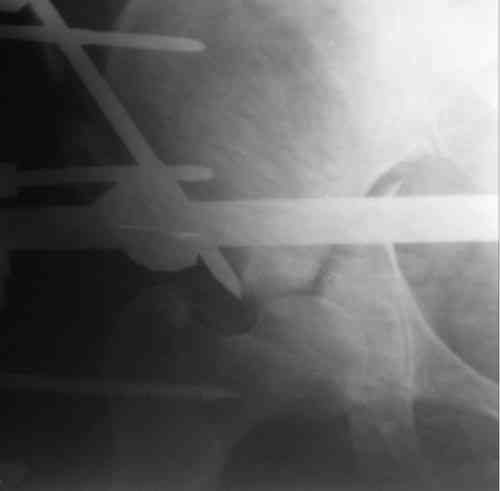

Пациентка 38 лет. В результате ДТП 02.09.06 получила поперечный перелом правой вертлужной впадины, центральный вывих правого бедра, разрыв правого крестцово-подвздошного сустава.

В одной из районных больниц вывих устранен, наложена система вытяжения по оси бедра и за вертельную область. Спустя 2 недели выполнен ВЧКО модулем "таз-бедро". Учитывая возраст пациентки и остаточный диастаз в области свода вертлужной впадины предполагается демонтаж аппарата, открытая репозиция и внутренний МОС вертлужной впадины через внутритазовый доступ.